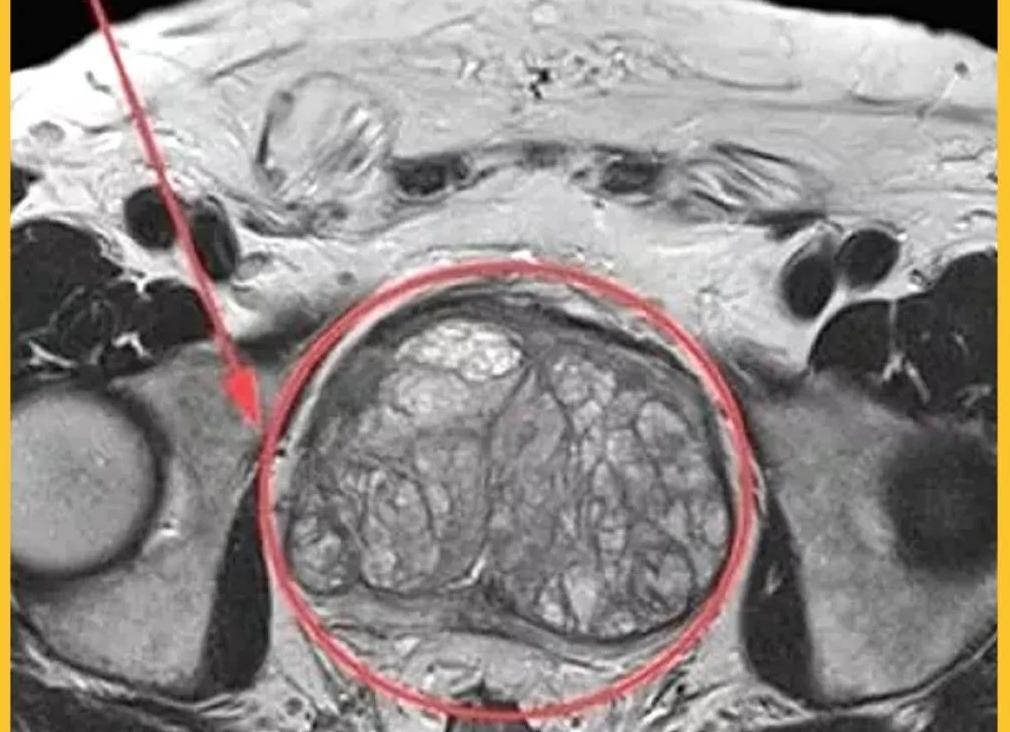

МРТ снимок простаты Заболевание развивается в результате увеличенной выработки клеток в тканях железы. С увеличением аденомы происходит сдавливание мочеиспускательного канала и, как следствие, нарушается процесс испускания мочи. Рост опухоли протекает медленно и ограничивается самой простатой.Долгое время процесс развития гиперплазии проходит бессимптомно, поэтому решающим фактором в успехе лечения заболевания является ранняя диагностика. МРТ аденомы простаты выполняется при подозрениях, связанных с объемными образованиями в малом тазу.МРТ – это точная, высокоскоростная и информативная диагностическая процедура исследования всей зоны интереса с выявлением сопутствующих осложнений и определением целесообразности оперативного (хирургического) вмешательства.Мнение, что аденома простаты влияет только на снижение сексуальной функции мужчины, ошибочно. В действительности, растущая опухоль чрезвычайно опасна и может привести к серьезным осложнениям. Появление характерных симптомов является сигналом к посещению врача-уролога:

Доброкачественная гиперплазия

Признаки болезни выявляют в зависимости от доминирующего компонента. Так, стромальная гиперплазия гипоинтенсивна на Т2-сканах, железистая – гиперинтенсивна. На фоне последней вероятны кистозные изменения в центре простаты. Ретенционные или поствоспалительные кисты чаще всего обнаруживают в периферической зоне. На фоне стромальной гиперплазии обнаружить онкологическое поражение центральных отделов особенно сложно.

При серьезной гиперплазии периферическая зона сильно сжимается, что приводит к хирургическому капсулированию предстательной железы. Опухоль тогда обнаружить чрезвычайно затруднительно.